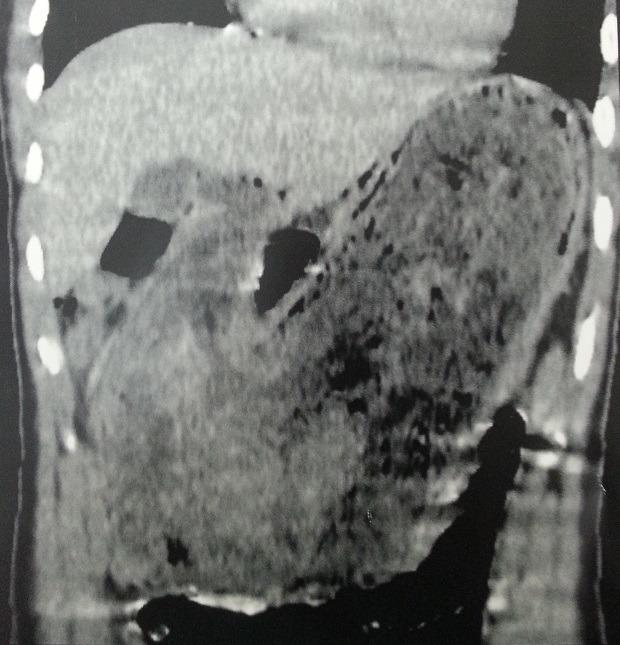

Rapunzel syndrome is an extremely rare complication of a gastric trichobezoar in. We report here the unusual case of a case of a 16 years old girl presented with severe abdominal pain and vomiting. Clinical examination revealed a malnourished girl, with presence of a mobile and sensitive abdominal mass of 20x15 cm witch filled the upper quadrant. An abdominal computed tomography scan showed a heterogeneous mass occupying the whole stomach cavity with extension into the third portion of the duodenum. A diagnostic of giant trichobezoar is suspected after further questioning reveling a trichotillomania, trichophagia and onychophagia. The removal of the trichobezoar endoscopically failed and it was possible to pull only few fibers of hair to comfort the diagnostic. She was subjected to an exploratory laparotomy. An antral gastrostomy were performed and a 25x10x7 cm trichobezoar was extracted. The patient had an uneventful postoperative outcome and was derived to psychiatry. Rapunzel syndrome is an uncommon trichobezoar, it's commonly found in young females usually with an underlying psychiatric disorder. Management requires gastrotomy. A psychiatric assessment and a long-term follow-up are advocated as a regular part of treatment to prevent recurrence.

长发公主综合征是胃内毛石极为罕见的并发症。我们在此报告一例不寻常的病例,一名16岁女孩出现严重腹痛和呕吐。临床检查发现该女孩营养不良,上腹部有一个可移动且敏感的20×15厘米腹部肿块。腹部计算机断层扫描显示一个不均匀肿块占据整个胃腔并延伸至十二指肠第三部分。进一步询问发现拔毛癖、食毛症和咬甲癖后,怀疑诊断为巨大毛石。内镜下取出毛石失败,仅能拔出几根毛发以支持诊断。她接受了剖腹探查术。进行了胃窦造口术,取出了一个25×10×7厘米的毛石。患者术后恢复顺利,并被转至精神科。长发公主综合征是一种罕见的毛石,常见于年轻女性,通常伴有潜在的精神疾病。治疗需要胃切开术。提倡进行精神评估和长期随访,作为预防复发的常规治疗部分。